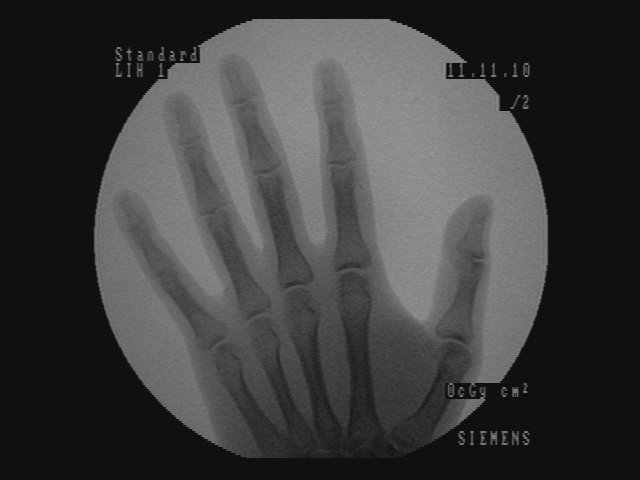

In Figure 5, for each scenario, one selected image Ilayerssubscript𝐼𝑙𝑎𝑦𝑒𝑟𝑠I_{layers} in the sequence can observed with different values of α𝛼\alpha, β𝛽\beta, γ𝛾\gamma and δ𝛿\delta. Each row i𝑖i corresponds to the sequence i𝑖i. From left to right, the layer visualized in Ilayerssubscript𝐼𝑙𝑎𝑦𝑒𝑟𝑠I_{layers} is getting closer to the X-ray source viewpoint. In the column (a), the furthest layer (the X-ray image) is displayed. In the column (b), the second layer (the background), in the column (c), the blending of the front layer with the background, in the column (d), the blending of the three layers and finally, in the column (e), the closest layer is shown. Additional images from the sequences can be visualized in the supplementary video where interaction between the layers by changing the blending values can be observed.

(a) (α,β,γ,δ)=(0,0,1,1)𝛼𝛽𝛾𝛿0011(\alpha,\beta,\gamma,\delta)=(0,0,1,1)

Refer to caption

(b) (α,β,γ,δ)=(0,1,0,0)𝛼𝛽𝛾𝛿0100(\alpha,\beta,\gamma,\delta)=(0,1,0,0)

(c) (α,β,γ,δ)=(0.4,0.6,0,0)𝛼𝛽𝛾𝛿0.40.600(\alpha,\beta,\gamma,\delta)=(0.4,0.6,0,0)

(d) (α,β,γ,δ)=(0.2,0.3,0.5,0.5)𝛼𝛽𝛾𝛿0.20.30.50.5(\alpha,\beta,\gamma,\delta)=(0.2,0.3,0.5,0.5)

(e) (α,β,γ,δ)=(1,0,0,0)𝛼𝛽𝛾𝛿1000(\alpha,\beta,\gamma,\delta)=(1,0,0,0)

(f) Inpainting

Figure 5: Per row i𝑖i, multi-layer image Ilayerssubscript𝐼𝑙𝑎𝑦𝑒𝑟𝑠I_{layers} of one selected frame in the sequence i𝑖i with different blending parameters (α,β,γ,δ)𝛼𝛽𝛾𝛿(\alpha,\beta,\gamma,\delta)

Similar to results from Habert et al. [6], the images resulting from synthesization are not as sharp as a real video image. The area synthesized by our algorithm is approximately 20 cm ×\times 20 cm (C-arm detector size), which is small compared to the wide-angle field of view from the Kinect v2. Reduced to the area of synthesization, the video and depth from Kinect is not of high resolution enough for sharper results. More specialized hardware with smaller field of view and higher resolution RGBD data would solve this problem. Moreover, several artifacts can be seen around the hand and surgical instruments in the synthesized image due to high difference and noise in depth in the RGBD data from the 2 cameras. However, our results demonstrate that our method is working well, since the incision line and cross drawn on the hand model and patient hand are perfectly visible in the recovered background image and can be seen in transparency through the hands and surgical tools in the images of Figure 5-column (c) and (d). In the scalpel sequence (sequence 6) in Figure 5-column (b), it can be seen that the tip of the scalpel is considered as background, this is due to the margin of few centimeters used for background segmentation. In this image, the scalpel is actually touching the skin.